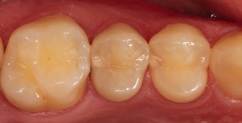

Bei dem 57-jährigen Patienten imponierte in der Routine-Bissflügelaufnahme eine Sekundärkaries an dem mit einem Gold-inlay versorgten Zahn 14 (Abb. 1). Der vitale und symptomfreie Zahn zeigte lediglich radiologisch (Abb. 2) einen Randdefekt distal sowie den Verdacht auf Karies unter dem Befestigungs- bzw. Unterfüllungszement. Nach Entfernung des Goldinlays ergab sich der Verdacht auf eine Pulpaeröffnung (Abb. 3). Klinisch war keine Blutung feststellbar, was allerdings durch die Lokalanästhesie kaschiert sein konnte. Aufgrund der Symptomlosigkeit des Zahnes und fehlender Anzeichen einer Pulpitis (fehlende Blutung) sowie einer Nekrose (erhaltene Vitalität) fiel die Entscheidung zugunsten einer Vitalerhaltung unter Beibehaltung eines engmaschigen Recalls mit Vitalitätsproben. Die Überkappung der Eröffnungsstellen erfolgte als Alternative zu Calciumhydroxid [8] mit einem Portlandzement enthaltenden Flowkomposit mit hohem pH-Wert [7,51] (TheraCal LC, Bisco, Abb. 4). Obwohl dieses Produkt hinsichtlich seiner Effektivität und Zelltoxizität nicht an ProRoot MTA (Dentsply Sirona) und Biodentine (Septodont) [42] herankommt [5,11], ist es hinsichtlich seiner Praktikabilität und der Möglichkeit des sofortigen, zügigen Weiterarbeitens konkurrenzlos. Ein vergleichbares Produkt gibt es z.B. bei Ultradent (Ultra- Blend Plus).

Die Weiterversorgung erfolgte nach adhäsiver Vorbehandlung mit einem approximal eingebrachten 4-mm-Inkrement SDR flow+ (Dentsply Sirona) in der Farbe A3, klassisch überschichtet mit ceram.x universal in der Farbe A3,5. Die Wahl auf ein Bulk-Flow-Komposit approximal fiel aufgrund der optimalen selbstnivellierenden Adhäsion zum Adhäsiv und somit zur Reduktion potenzieller Fehlerquellen in der Schichttechnik, die Wahl zugunsten des eingefärbten SDR flow+ in der Farbe A3 entgegen der transluzenten Universalfarbe U aufgrund der im Approximalraum dunkel erscheinenden Gold-Restauration am Nachbarzahn. Dies ergab in der Vergangenheit bei Verwendung von SDR flow+ U oft ein unschönes „grau-transluzent“ erscheinendes Bild der Kompositrestauration im Approximalraum. Ästhetisch störte dies meist nur bedingt, suggerierte aber immer die latente Möglichkeit einer Approximalkaries. Durch die Verwendung der Farbe A3 bei SDR flow+ war ein derartiges grau-transluzentes Erscheinungsbild nicht mehr gegeben; die Restauration erscheint homogener (Abb. 5). Die Abbildung 6 zeigt die Röntgenkontrollaufnahme nach einem Jahr, die Abbildung 7 die klinische Situation: Der Zahn ist weiterhin vital, symptomlos und beschwerdefrei. Direkte Kompositrestaurationen stellen heute gerade bei vorangegangenen Goldinlay-Kavitäten die suffizienteste Sekundärversorgung dar: Der vorhandene Federrand kann belassen werden und muss nicht in eine plane Stufe einer Keramikrestauration umpräpariert werden.